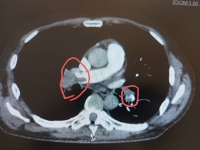

49-летний пациент был доставлен бригадой скорой медицинской помощи в клиническую больницу № 4 с выраженной дыхательной недостаточностью и положительным тестом на новую коронавирусную инфекцию. В связи с тяжестью состояния мужчина сразу же госпитализирован в реанимационное отделение больницы, где незамедлительно начато оказание медпомощи и обследование, по результатам которого выявлено жизнеугрожающее состояние - тромбоэмболия легочной артерии. При таком осложнении прогноз для жизни и выздоровления пациентов крайне неблагоприятный.

Современный 64-срезовый компьютерный томограф российской сборки смонтирован в больнице № 4 — новая техника заменила устаревший и выработавший свой срок эксплуатации 16-срезовый КТ. Это уже четвёртый томограф, установленный в этом году в больницах Волгоградской области.